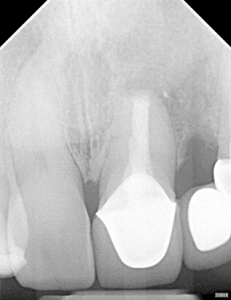

Clinical Cases